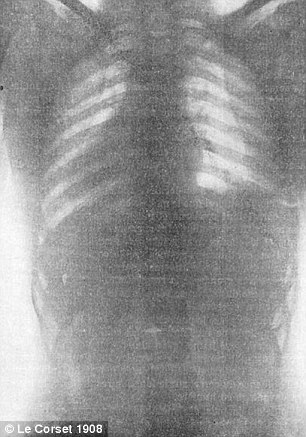

In radiografiile „normale” se pot vedea coaste paralele si organe pozitionate corect. In cele facute unor femei care au purtat corsete, descoperim coaste indoite si organe pur si simplu strivite.

„Corsetele comprima continutul torsului, in special inima si plamanii”, a explicat medicul Natalie Azar.